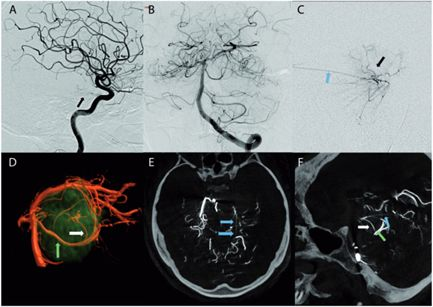

1、术前栓塞:用1毫升氰基丙烯酸酯胶(Glubran,Glubran-2,GEM,Viareggio,Italy)碘油(4ml of lipiodol)堵塞供血动脉,造影结果良好,无并发症。术后脑MR显示脑膜瘤部分断流,无脑水肿。

(患者脑血管造影图)

2、二天手术切除:颞部开颅术和前岩部切除术。脑膜瘤在肿瘤切除的不同阶段交替进行超声抽吸和周围结构的仔细解剖,从血管的角度观察,硬脑膜边缘被切断以完成肿瘤的断流。较终手术切除是完全的(辛普森I级切除),全部周围的颅神经IV、V、VII、VIII等均保存完好,患者术后神经功能完好。

图(a)为术前脑膜瘤影像图

图(b)为血管栓塞后肿瘤位置

图(c)、图(d)显示肿瘤已被完全切除